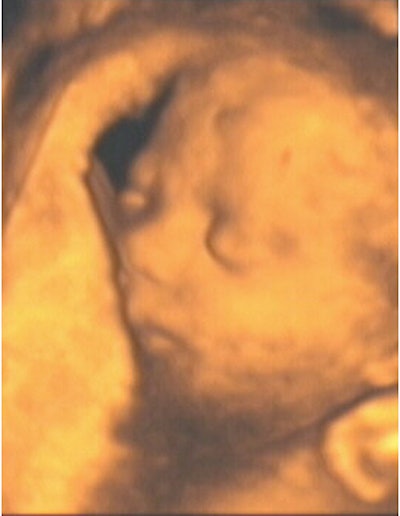

![]() |

| Figure 8, a 3-D ultrasound image of a fetus with hands in front of face at 21 weeks gestation. Image courtesy of Stefano Ciatti, M.D. |